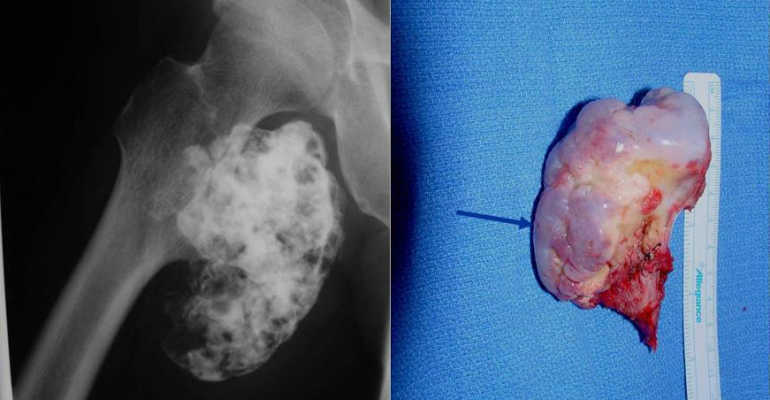

Остеохондрома бедра — дефект, возникающий на различных этапах формирования трубчатой кости. Она представляет собой плотное образование, структура которого схожа с диафизарной и суставной частью обычной кости. У остеохондромы блестящая, гладкая поверхность, образованная хрящевыми тканями толщиной около 0,1 см. Если новообразование формируется в детском возрасте, то по мере роста ребенка хрящевой слой истончается, а у взрослых может отсутствовать вовсе.

Внутри опухоль заполнена компактной костной тканью, а под ней располагается губчатая ткань. Костно-мозговое вещество находится в центральной части, связано с бедренной костью специальным каналом, состоящим из костного и мозгового вещества. В губчатых тканях расположены следующие структуры:

- единичные или множественные участки обезыствленных хрящей;

- аморфные массы;

- остеоиды — костные ткани, не подвергшиеся минерализации.

При проведении инструментальных исследований иногда обнаруживается сумка, сформировавшаяся над остеохондромой. Она содержит хрящевые тельца и отложения фибрина — высокомолекулярного, неглобулярного белка. Размеры опухоли — 2-12 см, но в медицинской литературе описаны случаи выявления и более крупных новообразований.

На рентгенографических изображениях хорошо просматриваются измененные контуры бедренной кости. Визуализируются и очертания новообразования — четкие, непрерывные. С помощью рентгенологического исследования не удается рассмотреть сформировавшуюся хрящевую оболочку, только если в ней нет очагов кальцификации. При подозрении на укрупнение хрящевого слоя пациентам назначается МРТ.